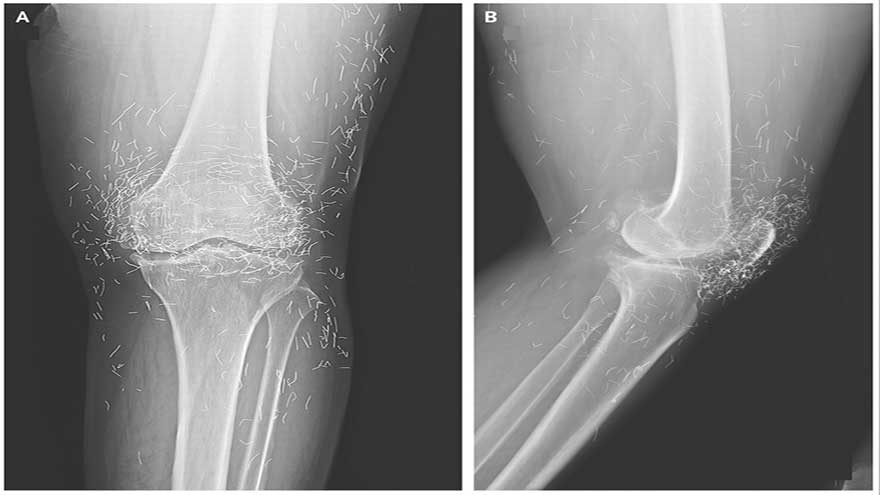

She later went to the hospital because her knees were very sore. X-rays of her left knee revealed that the shinbone in the inner part of the joint had thickened and hardened.

There were also bony growths, called spurs, on the inner portions of the shinbone and thigh bone by the knee joint.

The doctors also saw hundreds of flecks on the X-ray around the knee joint, which turned out to be tiny gold threads.

The diagnosis: The doctors learned that the threads had been inserted as part of the woman's acupuncture treatments. These short, sterile golden threads were purposefully left in the tissue to provide continued stimulation.